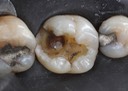

Kyle Chock #30 caries removal